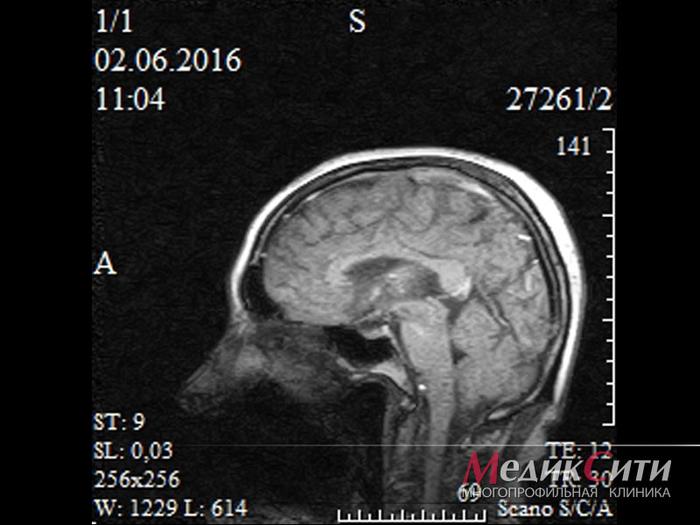

МРТ головного мозга

МРТ головного мозга

МРТ головного мозга